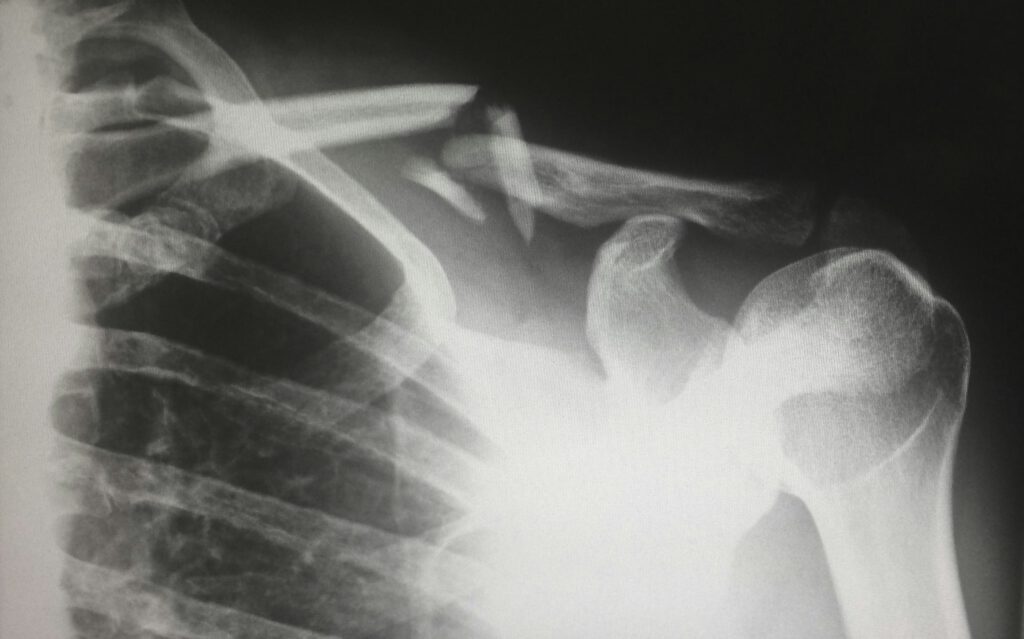

Der Effekt zeigt sich früh. Bereits innerhalb der ersten sechs Monate nach der Infusion steigt das Risiko. Es bleibt auch danach erhöht. Besonders häufig betreffen die Brüche die Hüfte oder das Becken. Typisch sind dabei auch sogenannte Ermüdungsbrüche, die sich schleichend entwickeln. „Eisencarboxymaltose war mit einem höheren Risiko für Knochenbrüche verbunden“, resümieren die Autoren der Studie.

Der Unterschied im Frakturrisiko bleibt bestehen, auch wenn Alter, Geschlecht oder Vorerkrankungen berücksichtigt werden. Patientinnen und Patienten mit Eisencarboxymaltose erleiden deutlich häufiger Knochenbrüche als jene mit dem Vergleichspräparat.